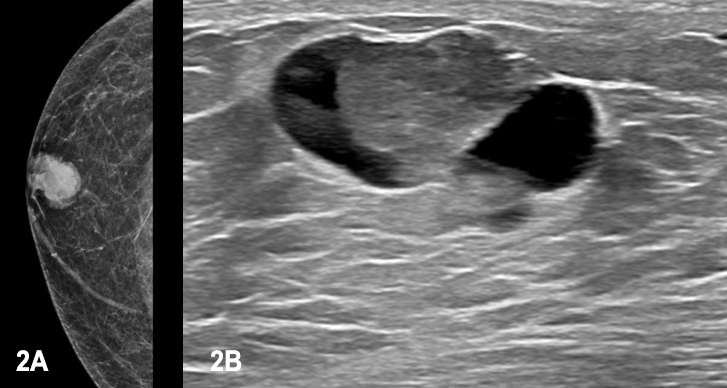

Case: Papillary Carcinoma Figure 2

Figure 2A, 2B. 66-year-old male presents for the evaluation of a palpable lump in the right breast. The right breast mammogram showed a lobulated oval mass with circumscribed margins measuring approximately 23 mm, which corresponded to the palpable lump clinically. Targeted sonography demonstrated a complex solid and cystic mass with circumscribed margins measuring 23 mm x 23 mm x 13 mm at 11 o’clock, 2 centimeters from the nipple. Excisional biopsy of the mass was performed which showed intermediate grade encapsulated papillary carcinoma with possible components of invasive carcinoma. Patient subsequently underwent mastectomy with final diagnosis determined to be encapsulated papillary carcinoma without invasive features.